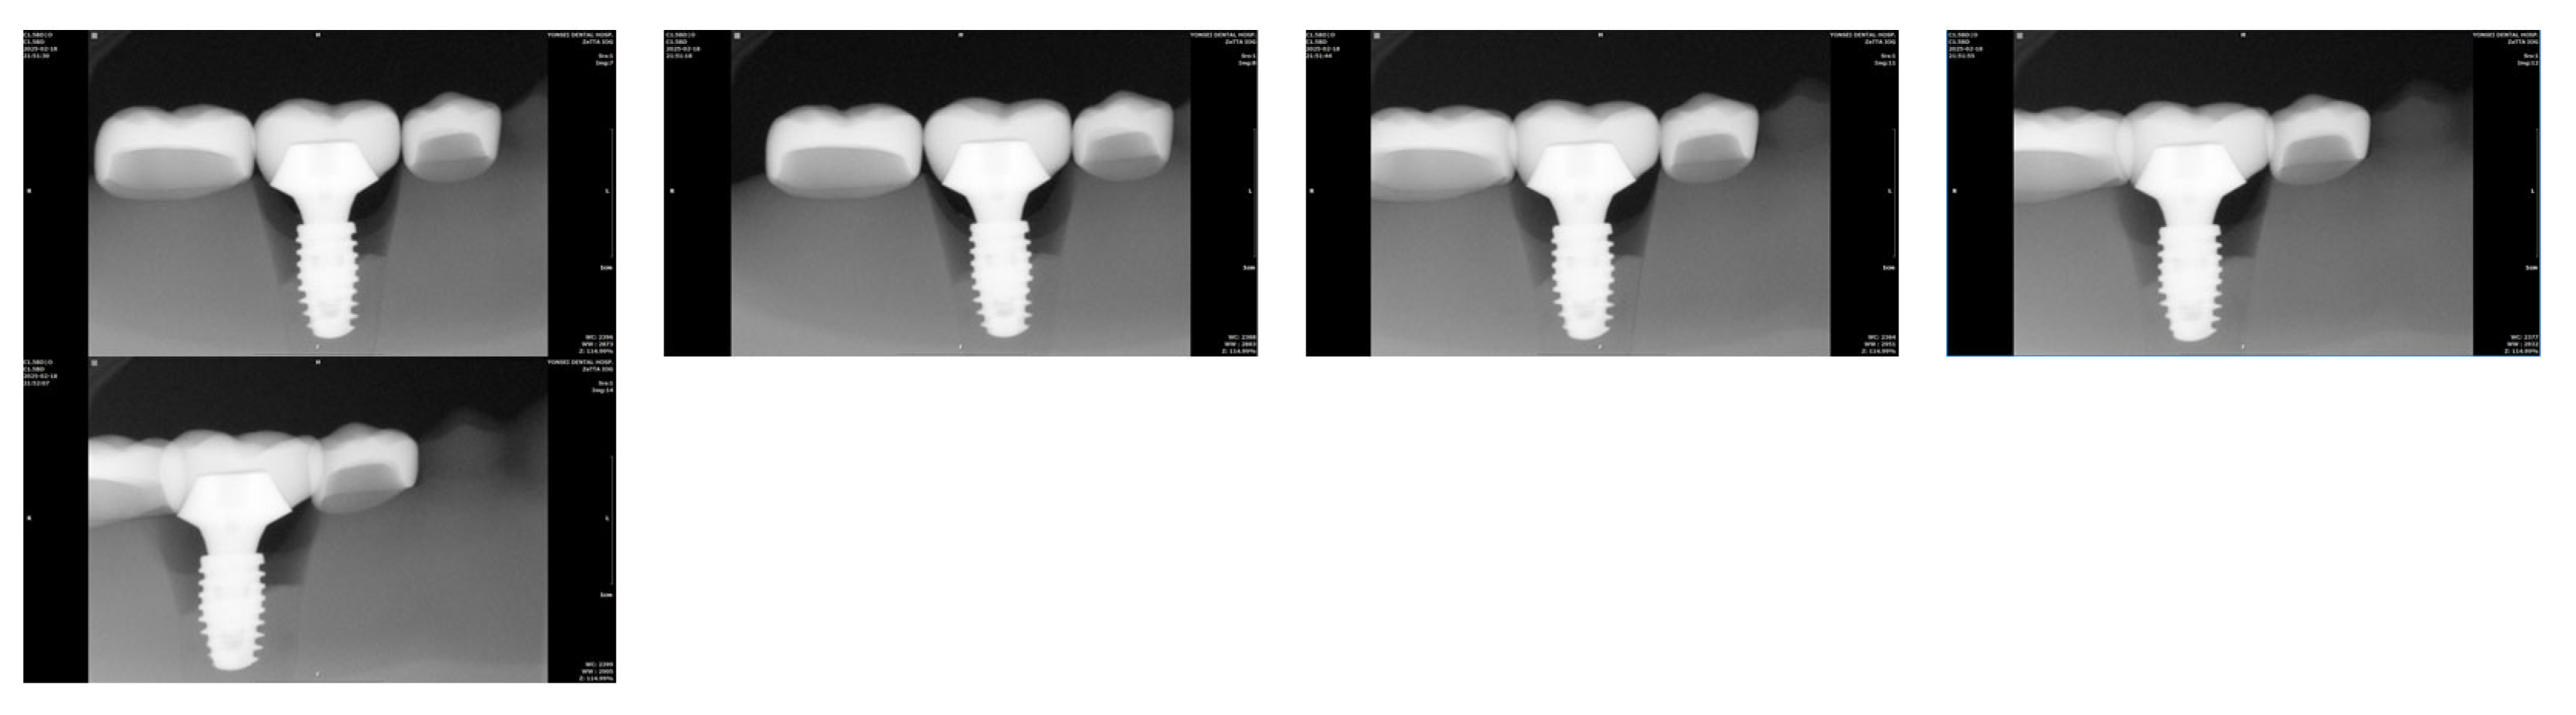

- With the implant positioned at the center of the residual ridge (Group Cent), the amount of interthread distance distortion was expressed as a percentage, using the measurement at 0° vertical angulation of the radiation tube as the reference. Figure 4 displays a series of periapical radiographic images acquired with the vertical rotation angle of the radiation tube set at 0°, 5°, 10°, 15°, and 20°, from the leftmost to the rightmost image, respectively. Each image was captured while maintaining the specified angulation during exposure.

Figure 4. Periapical radiographic images of Group Cent taken from left to right with vertical angulations of 0°, 5°, 10°, 15°, and 20°. As the vertical angulation of the radiation tube increases, the interthread distance also increases.